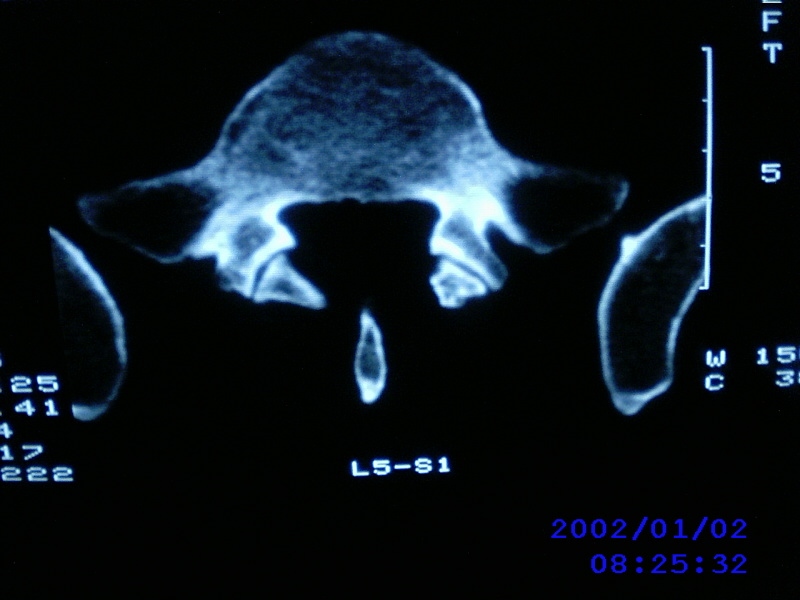

患者,男性,40岁,腰痛伴左下肢疼痛、麻木6年。5年前做过腰椎间盘手术,具体是哪个位置病人记不清了。

我拍的是l4-5、l5-s1

l5/s1术后

l4-5/l5-s1都做过。又有突出了

1)l4/5及l5/s1左侧椎板术后改变。2)l5/s1椎间盘突出,l5椎体下缘许莫氏结节。3)l4/5椎间盘膨出并突出。4)l3/4椎间盘膨出。